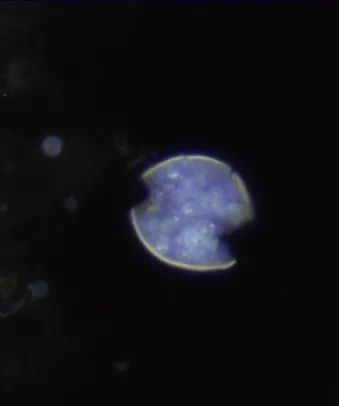

全血白细胞计数为13.4*109/L,血红蛋白8.5g/dL,血小板138/μL,C-反应蛋白28.8(正常值<3.0)。动脉血气分析显示pH值为7.30,PCO2为48.2,PO2为71.8,血培养呈阴性,进行BAL培养(包括细菌培养、病毒培养、真菌培养)。胸部X线及胸部CT显示弥漫性斑片状阴影(图1.2)。颈椎、胸椎和腰椎的CT扫描显示椎体病变(图3.4)。由于脾脏有多处病变,也进行了脾活检(图5)。

图5 脾活检:球状芽孢子破裂,内含完整的内孢子